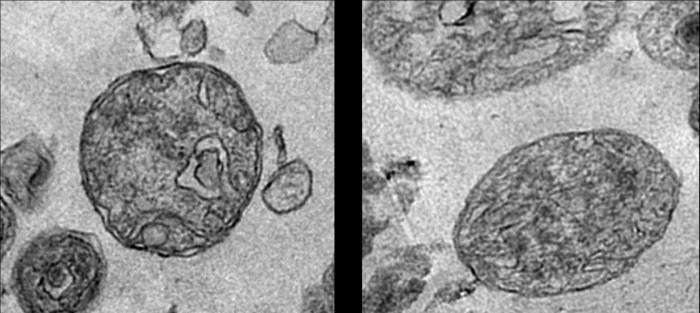

Но после семилетнего исследования команда IRCM теперь обнаружила полные и полностью функционирующие митохондрии в плазме крови, содержащиеся внутри высокостабильных структур. С помощью электронной микроскопии исследователи проанализировали образцы плазмы крови около 100 человек и обнаружили до 3,7 миллиона таких митохондрийсодержащих структур на миллилитр плазмы.